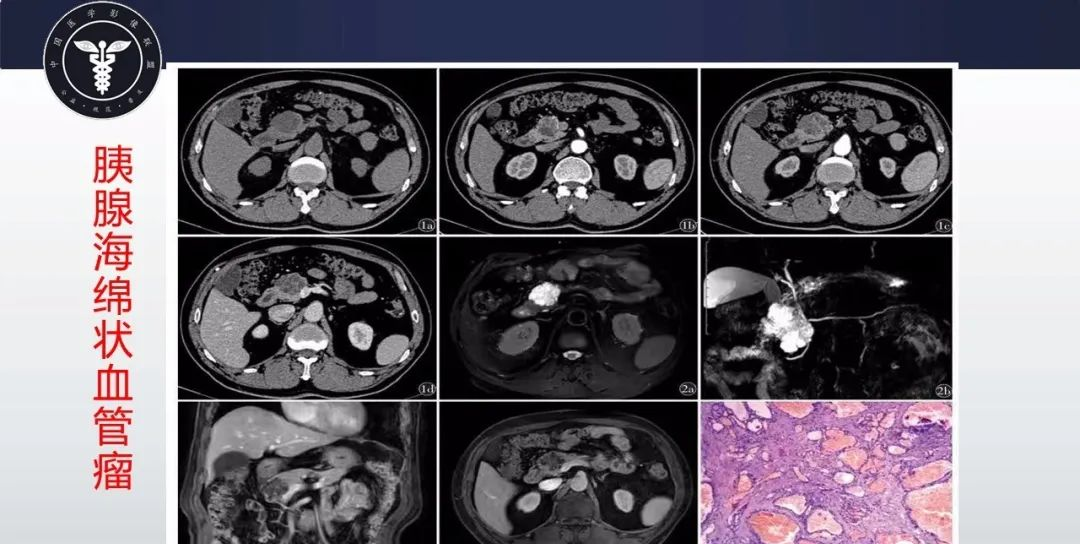

【病例】胰腺血管瘤1例CT及MR影像-1

【病例】胰腺血管瘤1例CT及MR影像-2

【病例】胰腺血管瘤1例CT及MR影像-3

【病例】胰腺血管瘤1例CT及MR影像-4